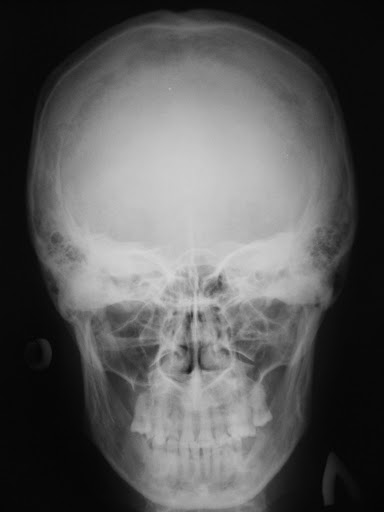

When you get a concussion, your skull may get thicker and we're not sure why фото